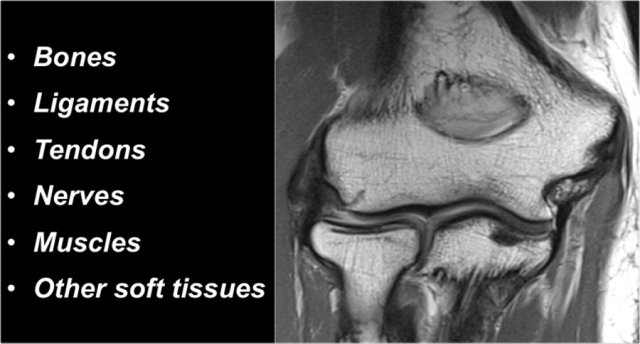

When you study the anatomy of the elbow, it is good to use the inside-out approach.

First study the bones and then continue with the ligaments and the tendons and then the surrounding structures.